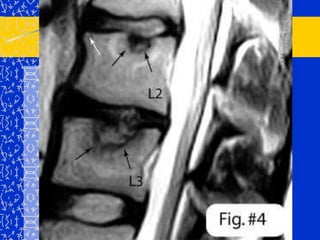

CIFOXIS CONGENITADebida a la falta de formación parcial o completa de la parte anterior de las vértebras y la falta de segmentación anterior de las vértebras adyacentes.Afectadas 1 – 3 vértebras, generalmente entre D10 y L2.

Cifosis Escoliosis